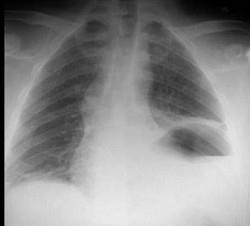

问题 35岁,男,因车祸入院,呼吸困难、发绀、上腹痛,请结合胸片和CT选择最可能的诊断 ( )

选项 A、膈麻痹 B、液气胸 C、胸腔积液 D、膈膨升 E、膈疝

答案 E